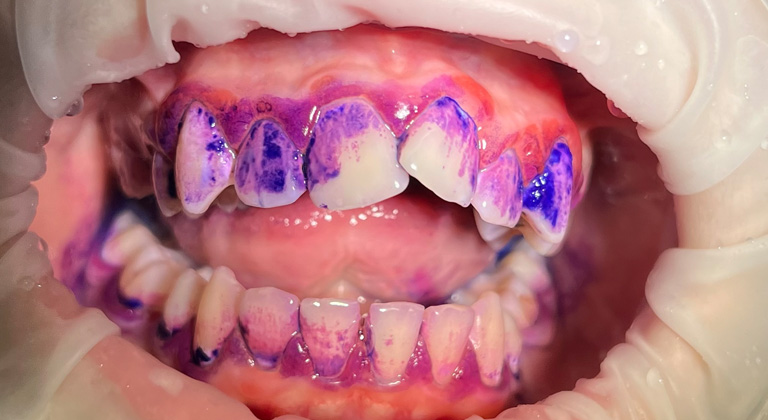

5. Wybarwianie płytki nazębnej

Wybarwienie płytki nazębnej pozwala na precyzyjną kontrolę stanu higienicznego jamy ustnej. Specjalna mieszanka wody i substancji wybarwiającej naniesiona na uzębienie wskazuje kolorystycznie te miejsca, w których znajdują się złogi bakteryjne. Taka analiza pozwala na dostosowanie odpowiednich narzędzi higienicznych do pacjenta. Pozwala też uświadomić go w zakresie nieprawidłowości wynikających z wykonywania codziennych czynności czyszczących.